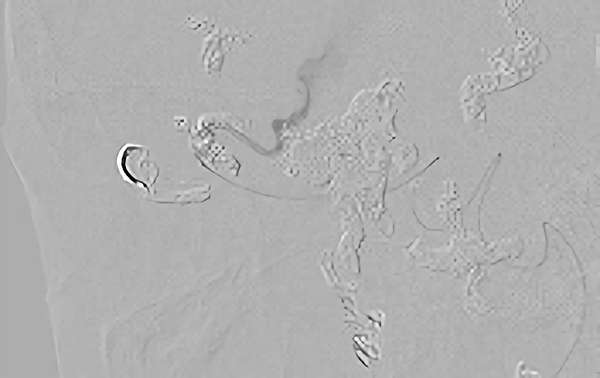

症例 '18年7月

No.

184

'18年7月17日

硬膜動静脈瘻

40代

大阪府の病院

手術写真

治療

前

中

後